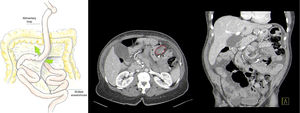

Varón de 41 años de edad, con antecedentes de bypass gastrica en Y de Roux acudió al serv. De urgencias por dolor abdominal difuso y nauseas. La TAC de urgencia demostró una hernia interna del intestino delgado a través del defecto de Petersen, entre el asa antecólia de la Y de Roux y el mesocolon transverso (fig. 1). Se puede apreciar la imagen arremolinada de los vasos mesentéricos alrededor del orificio de la hernia. La hernia interna relacionada con la derivación gástrica en Y de Roux es una urgencia quirúrgica poco frecuente que puede evolucionar. Hasta el estrangulamiento intestinal e isquemia. La presentación clínica es inespecífica, y el diagnóstico radiológico representa un reto. El tratamiento requiere la reducción del intestino incarcerado y el cierre del defecto.